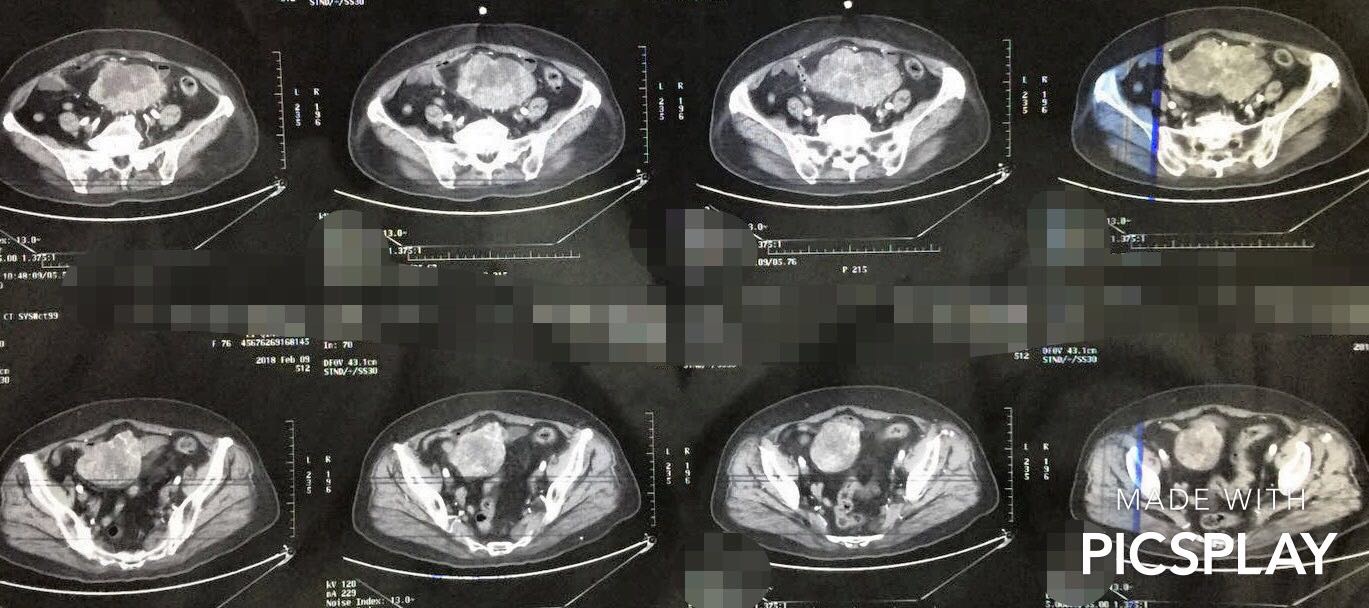

CT图示腹腔中下部较大类圆形肿物

CT表现:GIST在影像学检查表现为向腔外或腔内生长或沿胃肠壁浸润,大小不等,形态多为类圆形肿块,少数也可为不规则形,大部分边界完整。肿瘤体积较大的肿块内常常因为缺血坏死、或出血导致囊性变而显示低密度灶。肿块边缘可出现钙化,增强后实性部分多为中度以上强化,病变多数血供丰富,中高度强化,伴瘤周多迂曲供血血管。

腹腔内间质瘤(小肠间质瘤、小肠系膜间质瘤、大网膜间质瘤)

这几种间质瘤的诊断主要依靠腹盆增强CT来诊断,术前很难完全确诊。如果CT发现腹腔肿物,与小肠或大网膜关系密切,并且有间质瘤的特点,就可以做出初步诊断。此时,要重点排除其他部位恶性肿瘤导致腹腔转移,常见的就是胃肠道癌症转移或者妇科卵巢肿瘤转移到腹腔的结节。如果通过全面检查除外了其他器官病变,那么此时就可以考虑直接手术切除,术后根据病理诊断来确诊。但如果考虑 肿瘤巨大或与重要血管脏器粘连侵犯,手术切除困难时,需要腹腔穿刺取活检明确病理性质,药物治疗后再考虑手术切除。